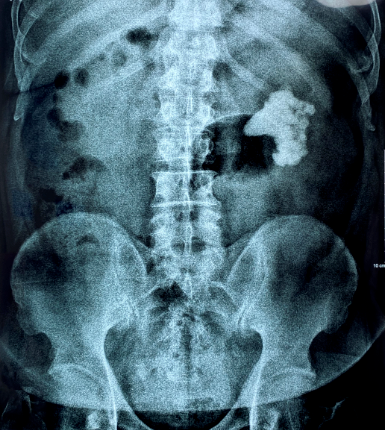

▲形态各异、大小不同、位置不同的泌尿系结石